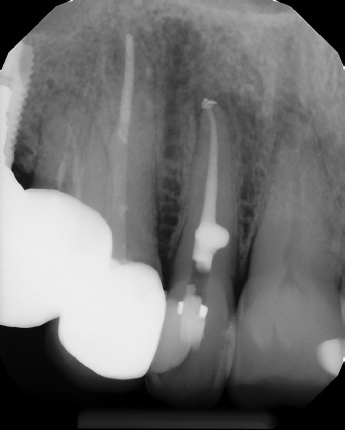

COMPLICATED ANATOMY LARGE LESIONS CALCIFIED CANALS PERFORATION / RESORPTION SEPARATED INSTRUMENTS SURGICAL CASES RETREATMENT / pOST REMOVAL OPEN APICES ACCESS THRU CROWNS Root Canal Case Portfolio

6 mos.